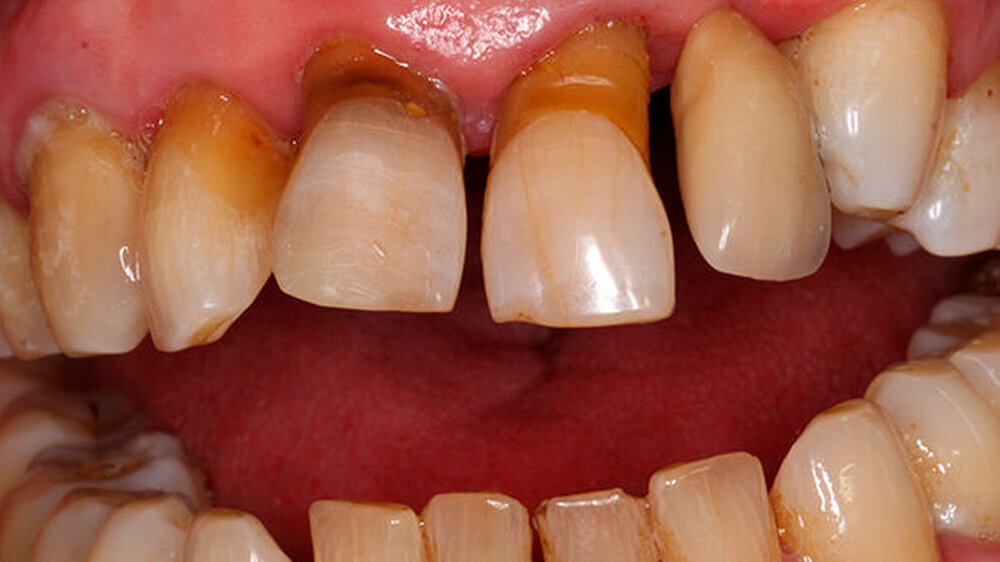

Ein 80 Jahre alter Patient stellt sich im September 2016 in der Poliklinik mit der Bitte um festsitzende Versorgung der Frontzahnlücke in Regio 22 vor (Abbildungen 1 und 2) Der Zahn 22 musste vor etwa einem Jahr parodontal bedingt extrahiert werden. Seitdem war diese Lücke durch einen Interimsersatz versorgt. Nach klinischer und röntgenologischer Befundung stellt sich schnell die Problematik dar, die im Rahmen der Versorgung dieser Frontzahnlücke auftreten wird.

Die Versorgung der Frontzahnlücke in Regio 22 wird intensiv mit dem Patienten diskutiert. Aufgrund des absoluten Mangels an ortsständigem Knochen, des hohen Patientenalters sowie der eher mäßigen Mundhygiene scheidet eine Implantation mit Knochenaugmentation aus. Hinzu tritt die starke, vor allem im Frontzahngebiet ausgeprägte Parodontitis. Ein langfristiger Erhalt des endodontisch versorgten 11 sowie des stark parodontal kompromittierten 21 erscheint unrealistisch.

Für eine konventionelle brückenprothetische Versorgung scheiden die Schneidezähne ebenfalls aus: Zum langfristig prognostisch sicheren Ersatz des 22 wären Extraktionen und mehrere Substanz-opfernde Präparationen unausweichlich. Aufgrund des hohen Patientenalters und des Ausscheidens klassischer prothetischer Rehabilitationsmaßnahmen wird die Frontzahnlücke mit einer Adhäsivbrücke aus Metallkeramik versorgt (Abbildungen 3 und 4).